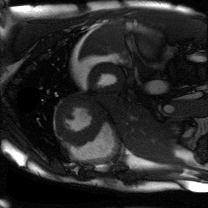

Supervised Deep-Learning (DL)-based reconstruction algorithms have shown state-of-the-art results for highly-undersampled dynamic Magnetic Resonance Imaging (MRI) reconstruction. However, the requirement of excessive high-quality ground-truth data hinders their applications due to the generalization problem. Recently, Implicit Neural Representation (INR) has appeared as a powerful DL-based tool for solving the inverse problem by characterizing the attributes of a signal as a continuous function of corresponding coordinates in an unsupervised manner. In this work, we proposed an INR-based method to improve dynamic MRI reconstruction from highly undersampled k-space data, which only takes spatiotemporal coordinates as inputs. Specifically, the proposed INR represents the dynamic MRI images as an implicit function and encodes them into neural networks. The weights of the network are learned from sparsely-acquired (k, t)-space data itself only, without external training datasets or prior images. Benefiting from the strong implicit continuity regularization of INR together with explicit regularization for low-rankness and sparsity, our proposed method outperforms the compared scan-specific methods at various acceleration factors. E.g., experiments on retrospective cardiac cine datasets show an improvement of 5.5 ~ 7.1 dB in PSNR for extremely high accelerations (up to 41.6-fold). The high-quality and inner continuity of the images provided by INR has great potential to further improve the spatiotemporal resolution of dynamic MRI, without the need of any training data.

翻译:在这项工作中,我们建议了一种基于IRI的方法,用这种方法来改进动态磁共振感应成像(MRI)重建,而该方法只是以高度低劣的 k-空间数据为基础,而该数据仅以磁共振坐标作为投入。具体地说,拟议的IRI将动态MRI图像作为一种隐含功能来表示,并将其编码到神经网络中。网络的权重仅从稀有的(k, t)空间数据本身中学习,而没有外部培训数据集或先前的图像。 利用基于IRI的强有力隐含性稳定化,同时不以清晰的动态和时空坐标坐标坐标坐标坐标作为投入。 拟议的IRIR将动态MRI图像作为一种隐含功能,将其编码到神经网络中。网络的权重仅从淡化的(k, t)空间数据本身学习,而没有外部培训数据集或先前的图像。